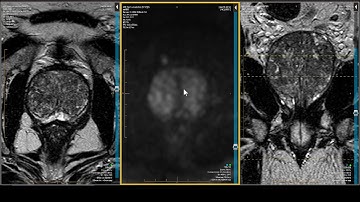

AI Tool for Prostate MRI Analysis to Support PI-RADS Scoring by RSIP Vision